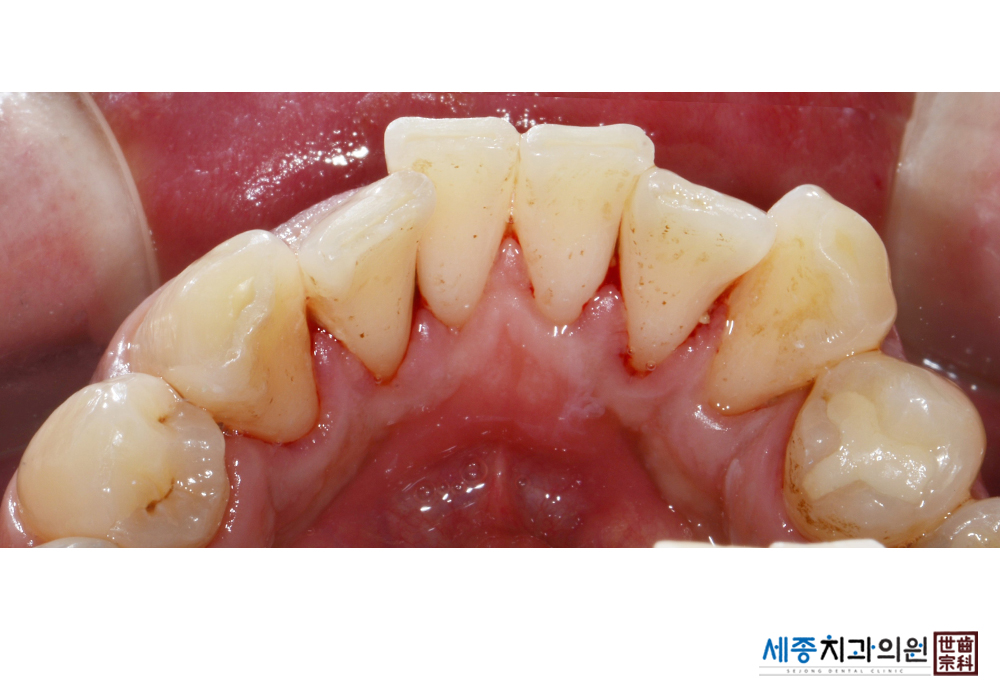

[스케일링] 치주질환 예방 스케일링

치료전 : 2020-02-12

가글마취&저주파 스켈러를 사용한 스케일링